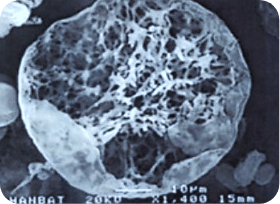

< 다공성 원형구조 미세분자 >

쥬베룩의 입자 형태

크기가 굉장히 작고 둥글기 때문에

결절이 잘 생기지 않고

생분해성으로 체외로 모두 배출되기 때문에

체내에 잔존물이 거의 남지 않습니다.